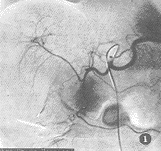

腹主动脉造影显示右侧肾上腺区少许肿瘤血管染色。选择性肾上腺动脉造影显示动脉期右肾上腺动脉不同程度增粗,肿瘤血管多而密集,呈网状,走行纡曲,粗细不均,以肾上腺中动脉造影时更明显。2例见少许静脉早显。实质期肿瘤染色浓密,不均匀。静脉期仍可见肿瘤较长时间淡薄染色(图1~3)。2例在血管造影中血压突然升高,达200~250/120~140 mmHg,伴恶心、腹痛,经降血压,镇痛等对症处理后,症状缓解。

图1 导管置于腹腔动脉开口处,造影显示肝、脾动脉形态,分布正常,右膈下动脉发出的右肾上腺动脉远段增粗、纡曲

图2 导管选择性插入右肾上腺中动脉起始部,造影显示动脉期大量增粗、增多、纡曲的肿瘤血管,可见少许静脉早显